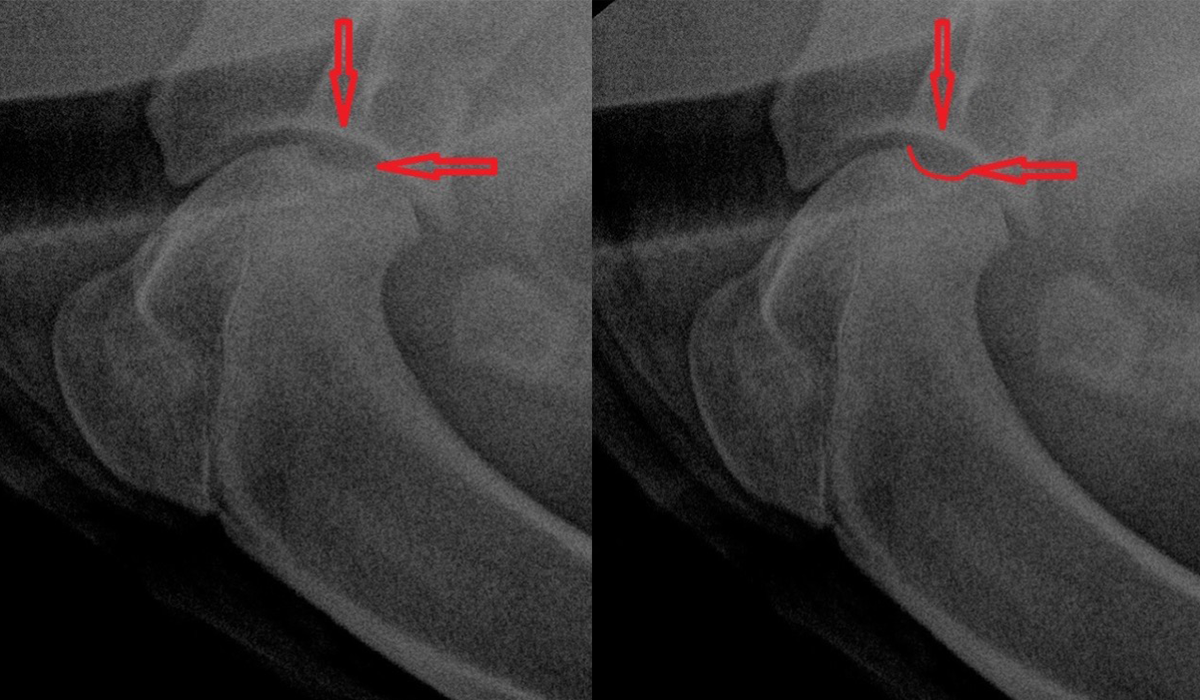

В норме поверхность головки плечевой кости без видимых прободений, эрозий и имеет ровную поверхность – отмечено зеленой линией.

При проявлении РОХ отмечается прободение (ямка) по месту отслоения хряща, что приводит к снижению его плотности на фоне нарушения сосудистого питания и визуализируется на рентген снимке как ямка – отмечено красной линией.